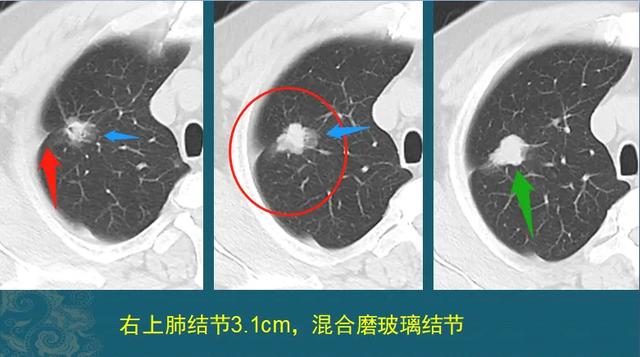

癌症从一开始就已经决定一个人的命运,治和不治都一样,是真的吗?插图1

这是一位30多岁男士,正是年轻力壮的好时候,也没什么症状,幸好单位组织体检,查出混合膜玻璃肺结节,ⅠA期肺腺癌。

癌症从一开始就已经决定一个人的命运,治和不治都一样,是真的吗?插图2

因为发现及时,手术完整切除,清扫淋巴结也没有发现转移,现在已经4年多了。

这种情况如果不治疗,很可能在未来一两年内进展到晚期,发生转移扩散,大大缩短寿命。